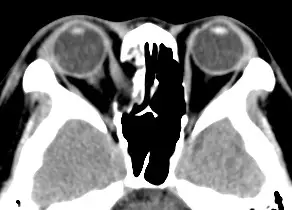

從提供的軸向CT影像可見:

- 右側眼眶底部(orbital floor)及內側壁(medial wall)處有明顯骨片缺損。

- Orbital fat及可能部分inferior rectus muscle已向下方的maxillary sinus突出,形成「fat herniation」徵象。

- 眼球位置相對偏後且周邊軟組織腫脹,對應病人臨床上描述的複視與右眼異常運動。

以上典型表現符合眼眶下壁及內側壁的blowout fracture,並伴隨內容物陷入旁側竇腔。